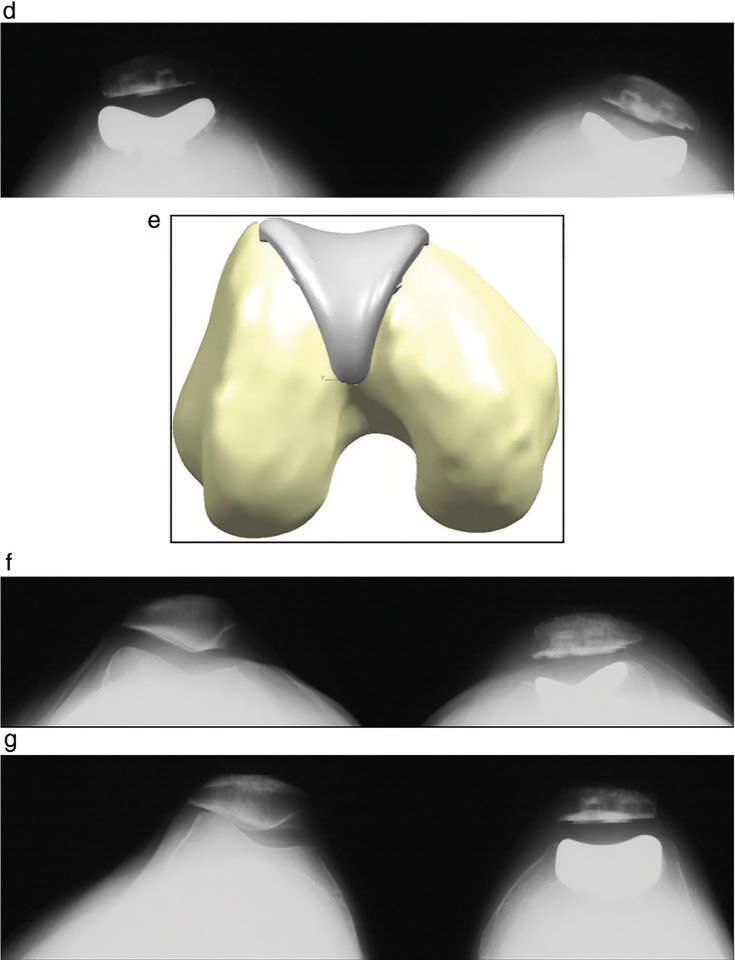

A patellofemoral arthroplasty maybe performed through any of the standard surgical approaches used for total knee arthroplasty such as midvastus and subvastus as well as parapatellar approaches. Importantly for PFA (patellofemoral arthroplasty) is the early activation of the vastus medialis obliques (VMO). This leads to early stabilization of the patella and the feeling of patient security. Many patients may well have laxity of the MPFL which may be deficient or pathologically lax. Some surgeons prefer a lateral approach in order to preserve any fibres remaining of the MPFL. However in terms of patella height unlike tibial TKA patients, PFA patients often have thin or deficient lateral patellae and reestablishing normal patella height with a polyethylene prosthesis will lead to tightening of the lateral soft tissue, particularly in absence of trochlea component external rotation. Here the surgeon should be aware that if a medial approach is used, a titrated lateral release or step cut lengthening of the iliotibial band and the capsule as well as the lateral patellofemoral ligament maybe required. Whereas lateral release is rarely required in modern total knee arthroplasty, the nature of the pathology and isolated patellofemoral disease should be in the mind of the operating surgeon as some form of lateral retensioning may be necessary. The majority of the patella implants are dome or oval dome rather than anatomically shaped. Therefore if a natural patella is resurfaced with a dome the resultant implant may cause tilting (figure 1). Therefore close observation of the lateral soft tissues is essential as tightening of the lateral capsule may be caused by inattention to patella resurfacing. Alternatively in the past the patient may have had an overzealous lateral release which may require retensioning or repair by the surgeon.

In trochlea preparation the first step would be to remove the synovium and osteophytes from the anterior femur and expose the most proximal extent of the trochlea. This will allow the surgeon to see directly the anterior femoral cortex and therefore the surgeon will make an appropriate judgement for the most posterior position of the trochlea cut. Surgeons should identify whether they are to use an inlay trochlea or an onlay trochlea. The more soft tissue aware surgeons are using inlay trochleas thus that they can match more accurately the articular contour of the trochlea without compromising soft tissue tension. (Figure 2 A – G).

This debate is a continuation of the discussion between TKA surgeons and the developing thoughts of PFA surgeons regarding trochlea component orientation. TKA methods call for a balanced flexion and extension gap which as indicated above, are tied to a tibial cut perpendicular to the long axis. To compensate for the natural tibial plateau varum, the femoral component is externally rotated when the knee is flexed to 90°. It is often taught that the aim in TKA is the ‘the grand piano’ sign that is produced when the anterior cut is at 3° of external rotation (2)The grand piano sign is consistently produced when surgeons use this technique to cut 3° of external rotation relative to the posterior condyle access or by resection parallel to the surgical epicondylar access (figure 4a). The butterfly sign (figure 4b) is produced by resection with 0° of external rotation relative to the posterior epicondylar axis (3).

One might imagine the grand piano sign would be desirable with PFA however it should be noted that PFA, is not one third of a TKA and operative techniques differ very significantly as does the surgical approach. The rational for external rotation in TKA is not to improve patella tracking, but to balance the flexion and extension gaps and therefore this technique may not pass directly to surgery of the patellofemoral joint. I believe that the trochlea should be orientated independently of the tibial femoral joint line or the anatomical axis of the femur and replicate only the orientation of the patients trochlear based on the patients anatomy. This debate still develops and therefore Farr has suggested some recommendations for the rotational position of the trochlear component.